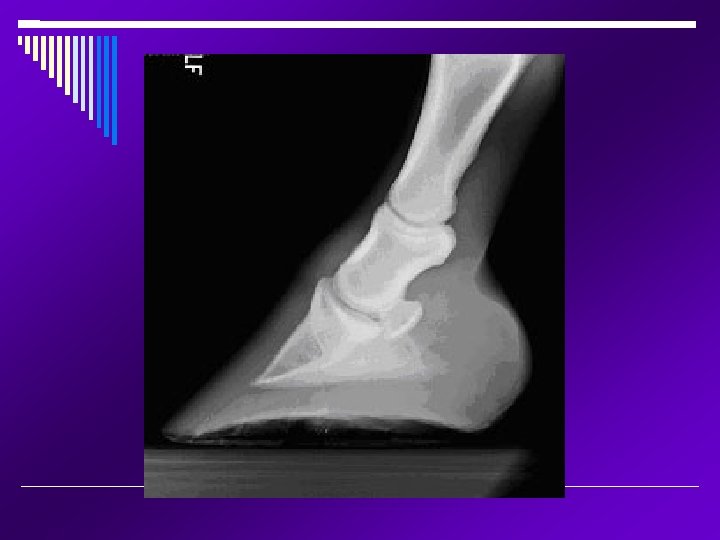

MRI Magnetic Resonance Imaging; the area being imaged is placed within a strong magnetic field and stimulated by radio-frequency pulses. These radio-frequency signals are collected analyzed by computers to form the image. Very, very costly and not widely available Anesthesia is required MRI tend to be superior to CT for soft tissue imaging The head, cervical spinal cord and lower legs can be imaged in an adult animal Precise and focal imaging tool that produces images of all tissue types; bone, tendons, ligaments, and fluid. Mainly utilized in equine lameness.